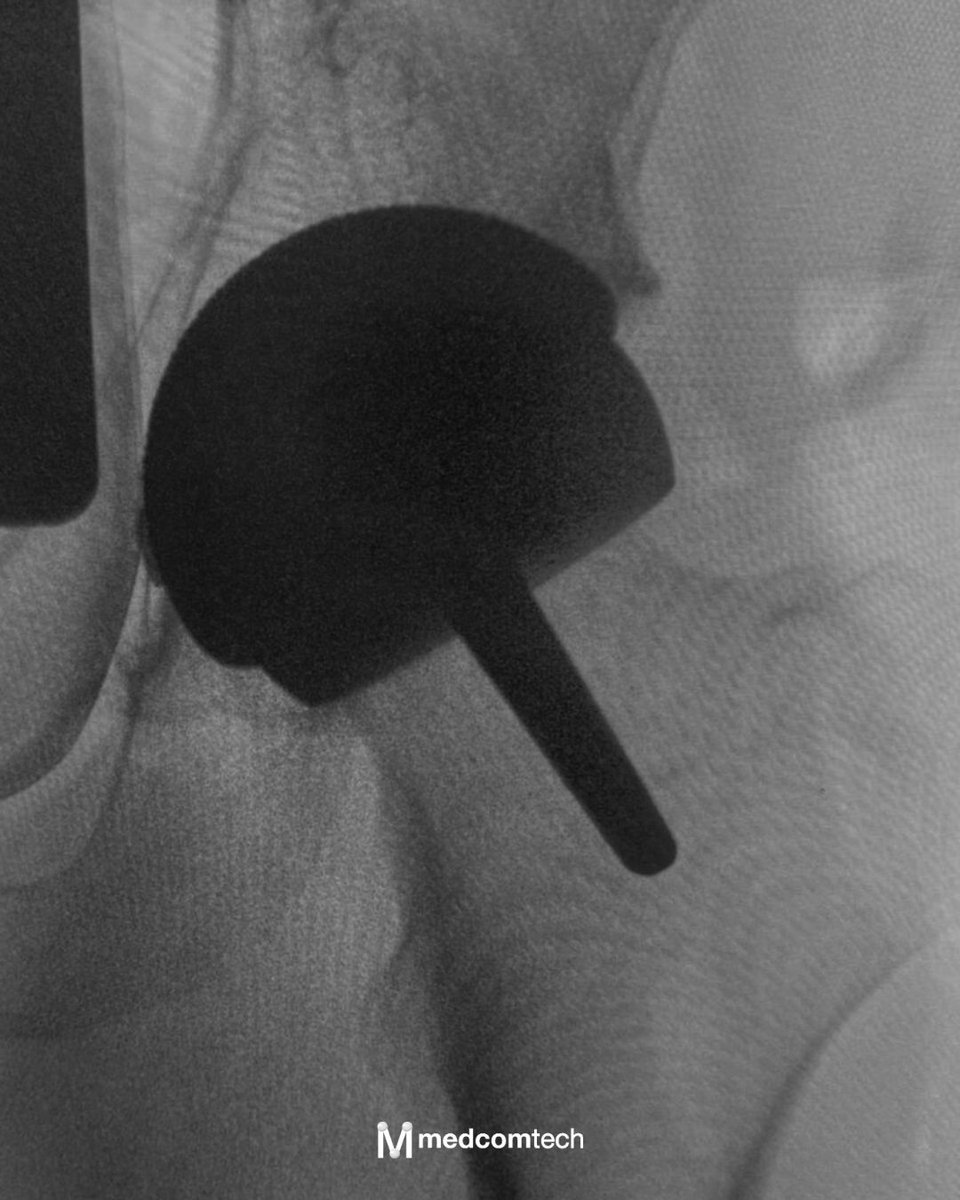

Nuevo caso de reconstrucción compleja de hombro con solución personalizada de @valor_implant

En @imed_hospitales se ha realizado una cirugía de prótesis invertida de hombro en un caso de gran defecto glenoideo que requería una solución específica de reconstrucción.